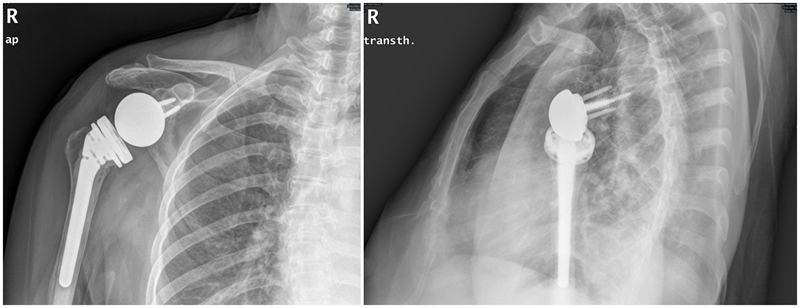

术后1年

图GIF5~7